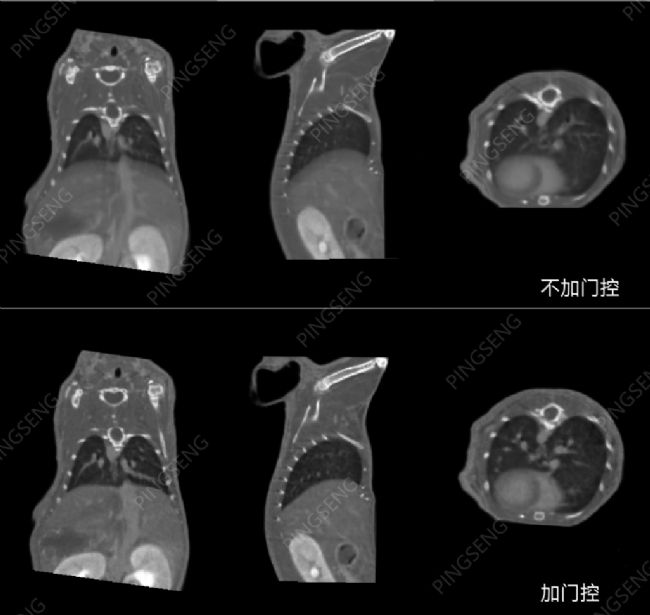

例1:通過門控技術(shù)的應(yīng)用NEMO® Micro CT掃描成像,可以有效地去除呼吸運(yùn)動導(dǎo)致的偽影,提高了CT圖像中器官邊界的準(zhǔn)確性。

圖1小鼠有無呼吸門控的對比圖